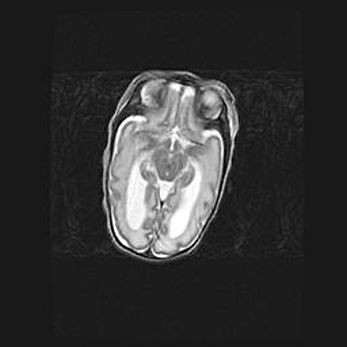

Множественные кисты обоих полушарий головного мозга, наибольшая из них в правой затылочной области. Ассиметричная атрофическая гидроцефалия.

Возраст: 7 месяцев

Вес: 5660 г

Пол: мужской

Окружность головы: 41,5 см

Срок гестации: 28-29 недель

Кисты головного мозга развиваются в результате многоочаговых некрозов вещества мозга и возникают вследствие перенесенной перинатальной инфекции, менингитов, энцефалитов, асфиксии, родовой травмы, расстройств мозгового кровообращения различного генеза. Образованию кист в веществе головного мозга плодов и новорожденных способствуют такие факторы, как высокое содержание в нем воды, недостаточная (или отсутствие) миелинизация и слабая астроглиальная реакция на повреждение.

Кисты могут сочетаться с гидроцефалией и другими поражениями головного мозга.